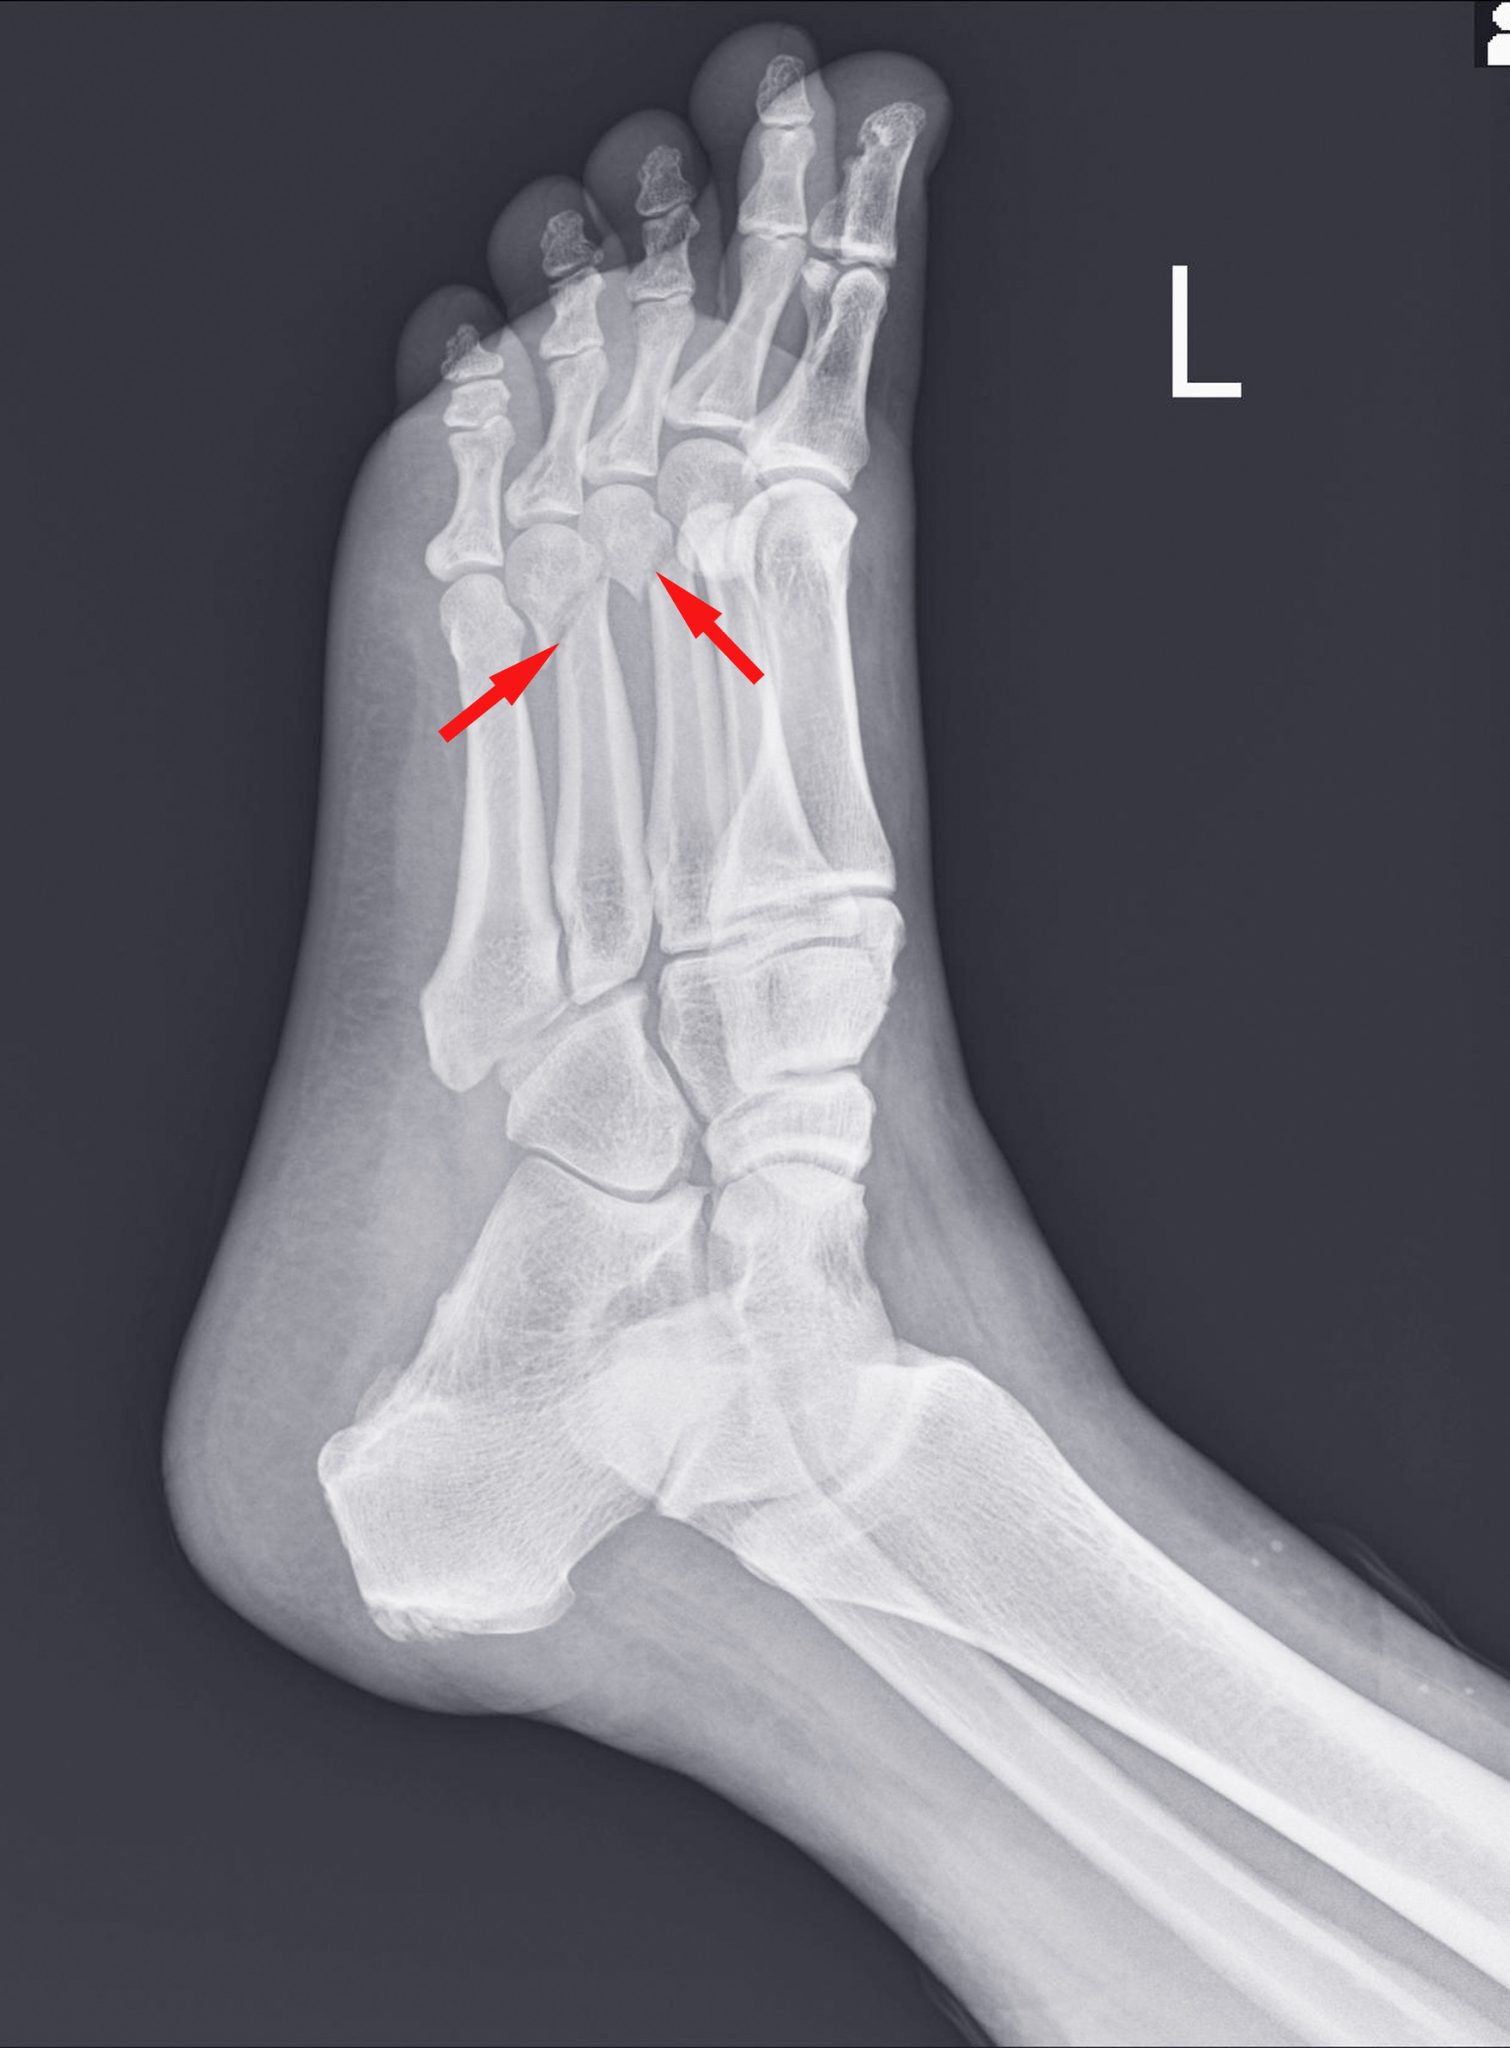

An X-ray of a foot with red arrows pointing to broken bones

The Most Common Ran Over Foot Injuries

Next, we look at some of the more common types of injuries you could experience after your foot was ran over by a car:

• Soft tissue injuries.

• Toe, ankle and foot fractures.

• Achilles tendon damage.

• Calcaneus fractures to the heel.

• Crush injuries.

• Partial or full amputation.

• Nerve damage.